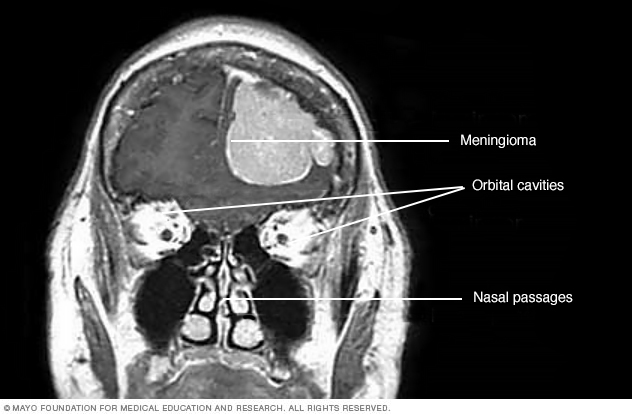

This contrast-enhanced MRI scan of a person's head shows a meningioma. This meningioma has grown large enough to push down into the brain tissue.